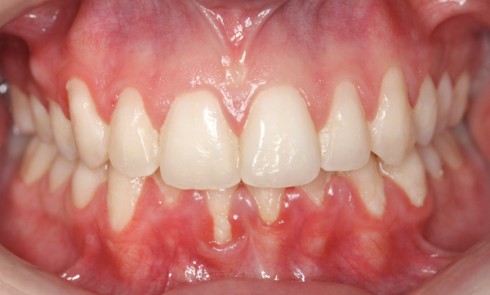

Article réservé à nos abonnés Le diagnostic muco-gingival en orthodontie : avant, pendant, après. Quand faut-il intervenir ?

L’un des objectifs de l’orthodontie est d’améliorer l’architecture dento-parodontale et par là même prévenir la survenue de pathologies parodontales sur...